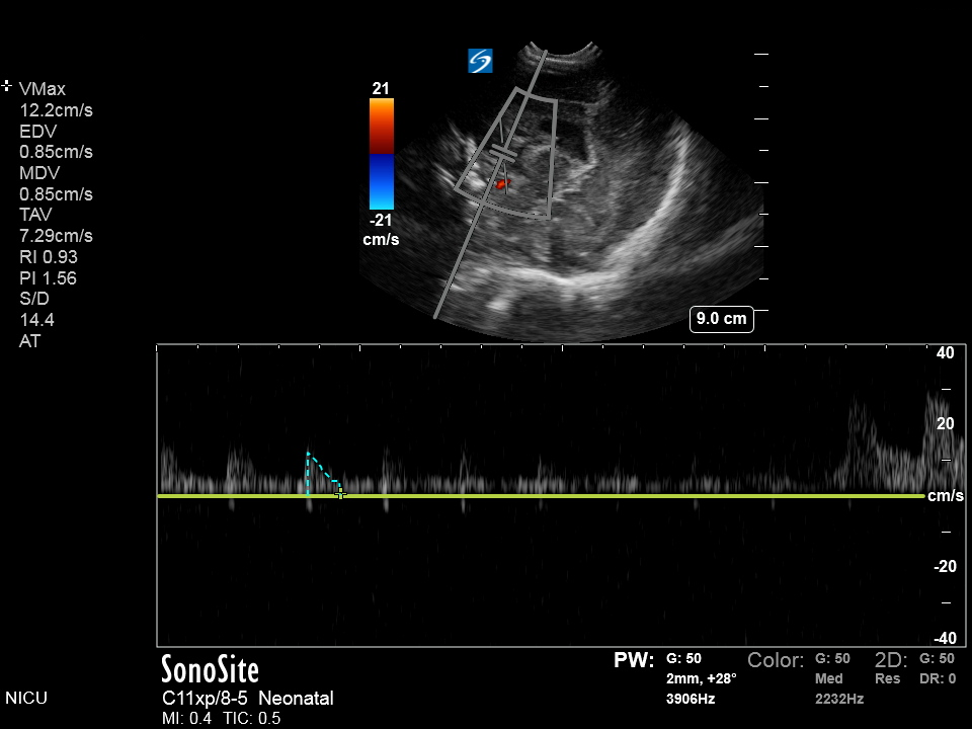

Neonatology Hydrocephalus Compression Test C Image